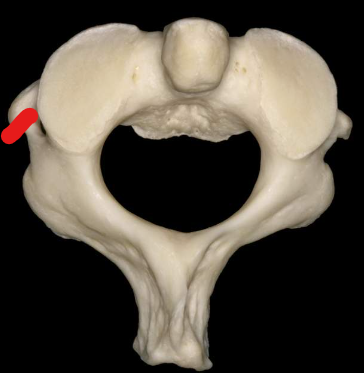

Atlas

Anterior tubercle

Anterior arch

Superior articular facet

Transverse foramen

Posterior arch

Posterior tubercle

Lateral masses